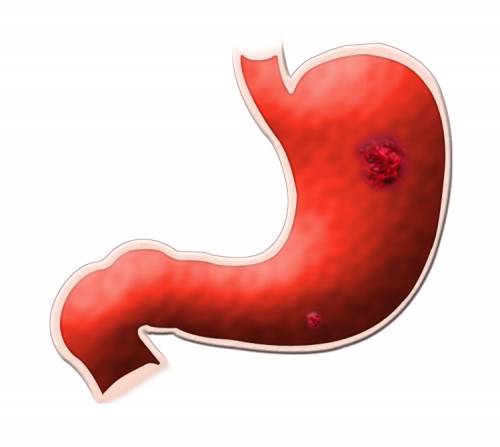

Early Gastric Cancer In The Stomach Photograph by Gastrolab

Stomach Cancer Photograph by Zephyr/science Photo Library

Stomach Cancer

What Is The Stomach Cancer